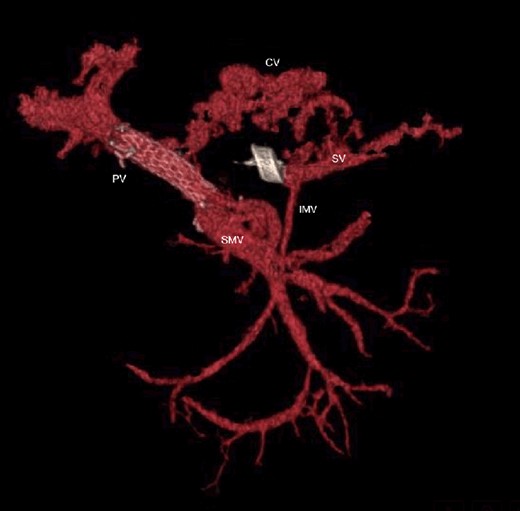

CT scan after other interventional radiology with plug in the splenic vein and cover stent in the superior mesenteric vein. PV portal vein, SMV superior mesenteric vein, SV splenic vein, IMV inferior mesenteric vein.

CT scan at 3 years, with development of venous collaterals that drain distal splenic vein and inferior mesenteric vein through the lesser omentum. PV portal vein, SMV superior mesenteric vein, SV splenic vein, IMV inferior mesenteric vein, CV collateral veins.